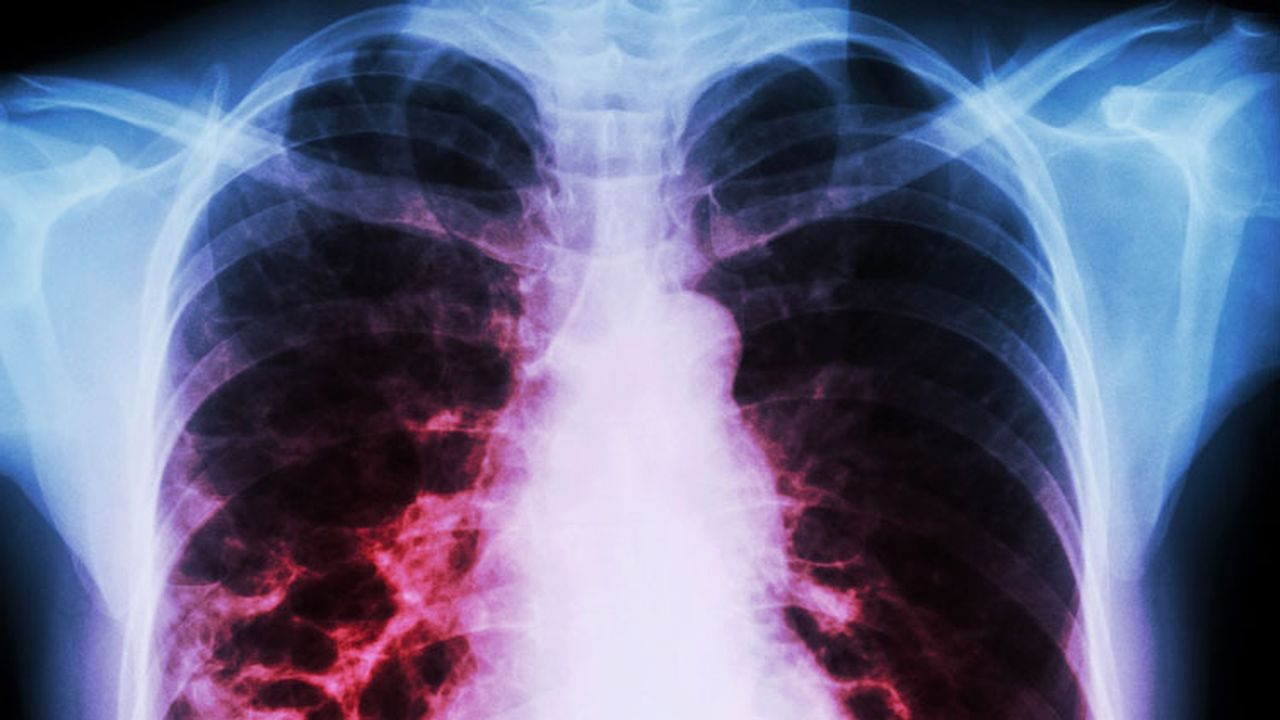

Covid-19 has been extensively studied and confirmed as a virus that affects people’s respiratory systems. Generally speaking, this denotes that the lungs are not spared and are the primary zone for the virus. In turn, this portends a highly serious illness as individuals may be considered to be in a very serious state without appropriate breathing or usually the circulation of oxygen, which may result in the collapse of other bodily organs and generally death. The rates of infection might be described as mild, severe, or even serious cases. The mucous membrane that lines the inside of the nose, as well as the ones in the eyes and mouth, are said to have originally come into contact with the infection. The healthy cells are then impacted and utilized to produce new viral components. Following that, these new cells multiply and spread to other areas.

Many people are afraid to visit hospitals because of the severe nature of some cases of Covid-19 infection to the lungs, therefore they instead opt to purchase kits. Self-testing kits like the PCR are available when necessary, however, before purchasing the kits, a person should be aware that additional lung scans are required to determine the severity. Additionally, more exploratory tests are required since they will assist isolate genetic material from additional samples. The worsening of the pulmonary swellings, which are then filled with fluid and debris, therefore sums up the effect of the Covid-19 severity level at this time. Mucus and other cells will then fill the air sacs. The body will then struggle to try and absorb oxygen as a result.

The linings and walls of the air sacs of infected people’s lungs have been damaged, demonstrating the severity of the infection at this stage. Even so, the body keeps fighting the infection, but as a result, the lungs swell or become inflamed, making it even more difficult for oxygen and carbon dioxide to circulate in and out of the lungs. That is extremely dangerous and requires urgent attention. At this juncture, individuals may develop acute respiratory distress syndrome (ARDS), which is one of the listed effects of COVID-19 on the lungs in terms of severity. So, in order for people to breathe correctly, machines may be needed.